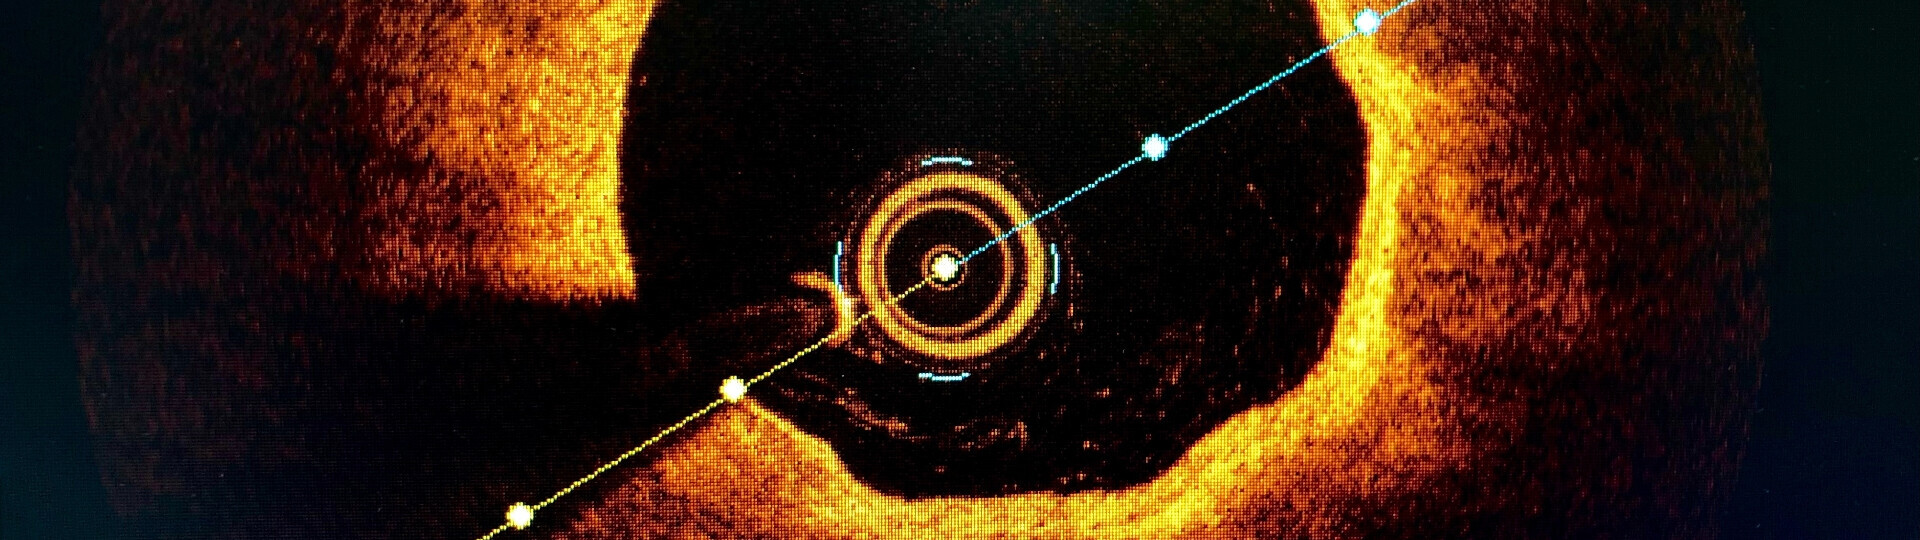

OCT, IVUS oder Angiographie? Die beste Bildgebung bei PCI

Auf dem ESC-Kongress wurden mehrere Studien vorgestellt, die den Nutzen der intravaskulären Bildgebung im Vergleich zur Koronarangiographie bei perkutaner Koronarintervention (PCI) verglichen. Dr. B. Hadley Wilson leitete die Hot Line Session 4 mit und fasst die Ergebnisse der Studien ILUMIEN IV, OCTOBER, OCTIVUS sowie einer Netzwerk-Meta-Analyse zusammen.

Bildquelle (Bild oben): BelezaPoy / Shutterstock.com